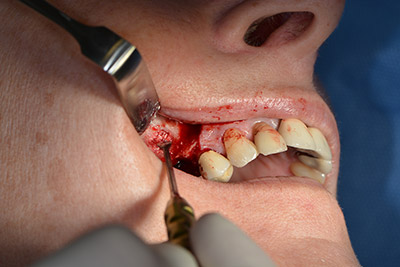

The classic incision (crestal, buccal relief) and the preparation of the mucoperiosteal flap enabled a good overview.

Sky implants (bredent) were used in this case. The surgical protocol of these, specify pilot drilling at about 1200 rpm (Fig. 9).